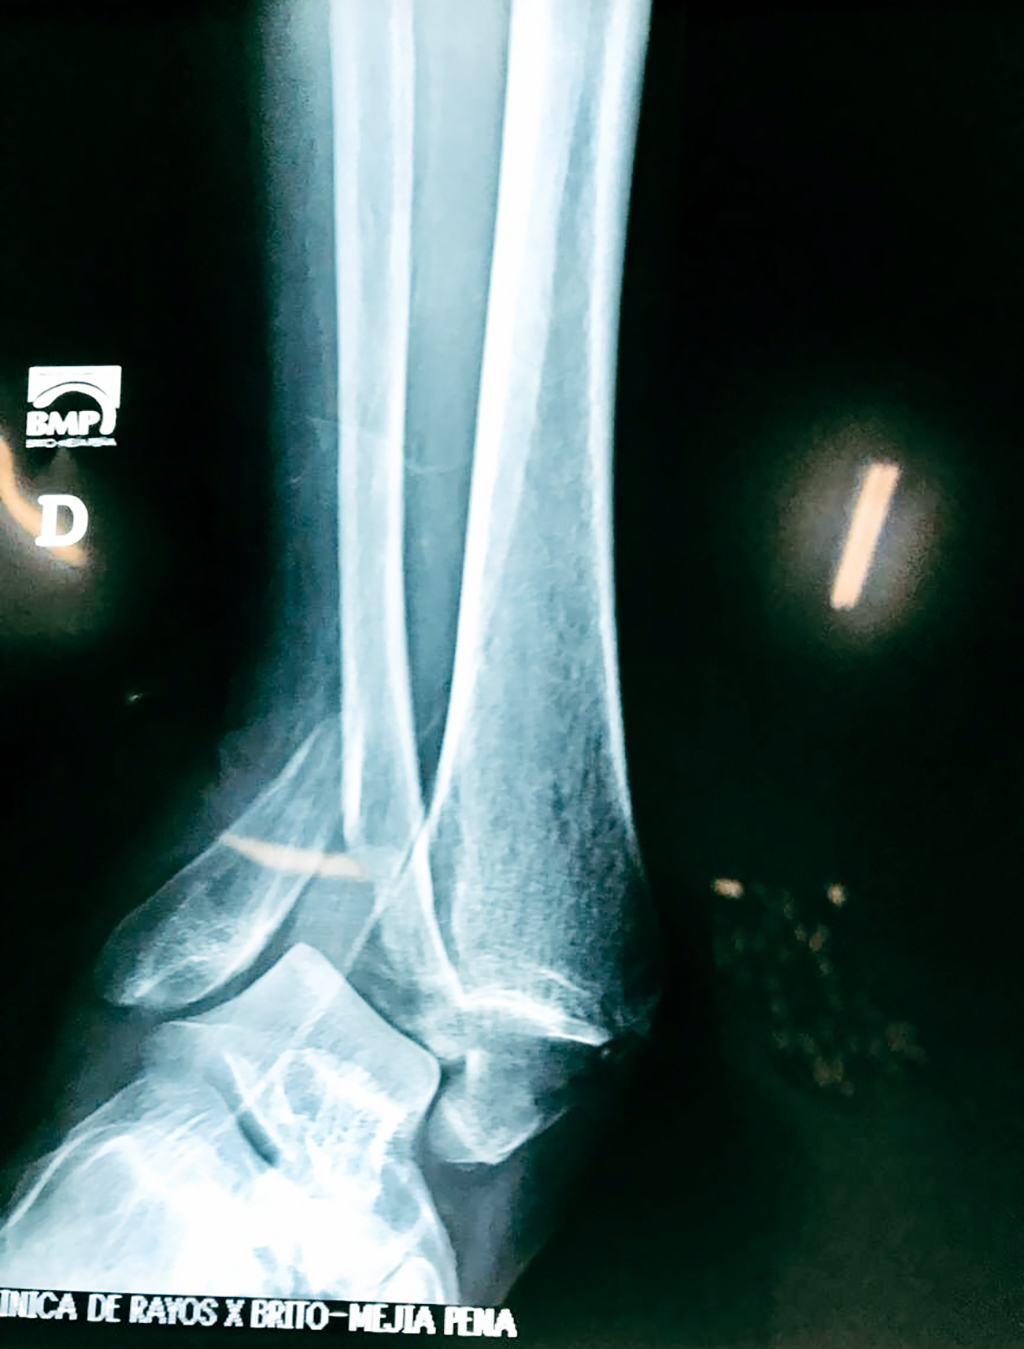

Una fractura de tobillo es la rotura de uno o más de los huesos del tobillo. Estas fracturas pueden ser:

- Completas (el hueso está perforado y está en 2 partes).

- Los extremos de los huesos están desalineados entre sí (desplazados).

- Los tendones o ligamentos (tejidos que sujetan los músculos y los huesos entre sí) están rotos.